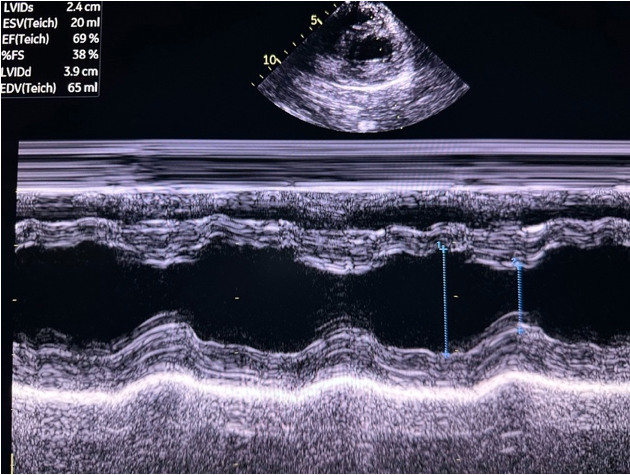

PSAX M-Mode

At the mid-papillary level, placing M-mode across the LV walls produces a motion trace of the septal and posterior walls throughout the cardiac cycle with distance displayed on the y-axis and time on the x-axis. The tracing shows the walls coming toward each other during systole and moving apart during diastole, with the LV cavity changing width in between (figure 15).

Figure 15: M-mode of the PSAX mid-papillary level

This pattern forms the basis for calculating fractional shortening (FS), which describes how much the LV diameter decreases during contraction, and linear EF, which measures volumetric change(figure 16). The FS and EF can be used to semi-quantify LVfx.

Measurements for FS and linear EF should be obtained at a single timepoint along the x axis corresponding to end-diastole and end-systole, rather than by selecting maximal wall excursion at different timepoints. Measuring the septum and posterior wall at different points of maximal excursion can result in inaccurate LV dimensions and overestimation of systolic function. It is also imperative to avoid placing the M-mode cursor through the papillary muscles, to ensure the true endocardial excursion is captured.

FS: percentage decrease in the LV diameter during contraction

Figure 16. LVIDd and LVIDs caliper placement for FS/EF calculation in PSAX M-mode

What is Normal & Not Normal

- Normal values for FS in infants and children are typically between 28% and 46% [18,22] (figure 17).

- A FS <28% is generally considered abnormal. This can be further categorized into mild, moderate and severe systolic dysfunction (table 3) [22] (Figure 18).

- In pediatrics, normal EF is ≥ 55% (figure 17)[23].

Figure 17. PSAX M-mode normal FS and EF